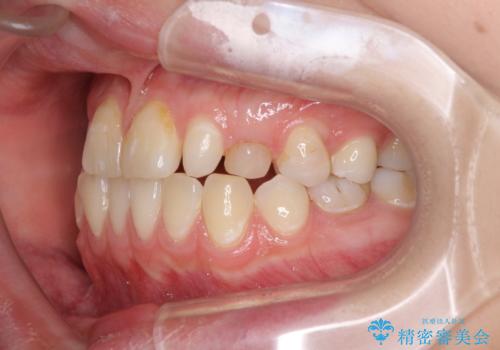

欠損と残存乳歯 矯正治療とインプラント治療

- 残存した乳歯や歯の欠損、歯並びを気にして来院された患者様です。

乳歯を残した状態は予後がよくないこと、矯正治療と補綴治療を総合的に進めていきたいとのことで、インビザラインによる矯正治療とインプラント補綴治療を並行して進めていくこととしました。

当院は矯正治療もインプラント補綴治療も、同一の歯科医師が担当するため、矯正治療を行いながら、最適なタイミングでインプラント補綴治療を行うことが可能です。